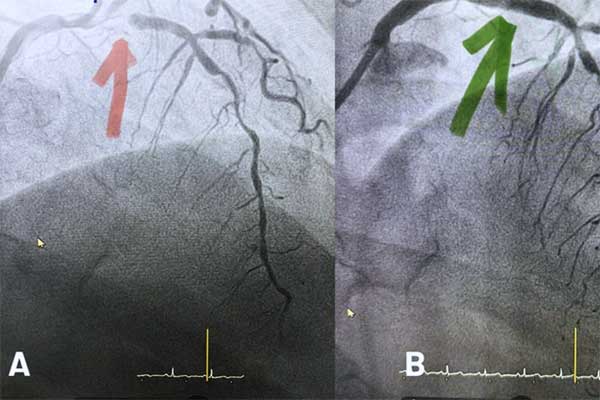

Hình ảnh đo điện tim cho thấy bệnh nhân có dấu hiệu nhồi máu cơ tim cấp do tắc động mạch vành trái, kèm sốc tim và suy đa tạng sau ngưng tim kéo dài. Ekip các chuyên khoa Tim mạch can thiệp, Hồi sức cấp cứu, Hồi sức tim mạch đã phối hợp điều trị cho bệnh nhân.

Cụ ông vừa được tái thông động mạch vành, vừa được can thiệp oxy hóa máu màng ngoài cơ thể (VA-ECMO) kết hợp phương pháp hạ thân nhiệt để bảo vệ não. Sau hơn 10 ngày điều trị tích cực, sức khỏe người bệnh dần ổn định và được xuất viện.

Bác sĩ chuyên khoa 1 Hồ Thị Tuyết Mai, Trung tâm Tim mạch cho biết, qua thực hiện các cận lâm sàng, bệnh nhân được phát hiện có dấu hiệu nhồi máu cơ tim cấp tính, do sự tắc hẹp của một nhánh động mạch vành.

Lập tức, bệnh viện kích hoạt ekip can thiệp mạch khẩn để cứu người bệnh khỏi nguy cơ đột tử. Ca can thiệp diễn ra vào nửa đêm. Ekip điều trị đặt 1 stent tái thông động mạch liên thất trước. Ngay sau thủ thuật, bà T. hết hẳn đau bụng, hồi phục hoàn toàn và xuất viện 2 ngày sau đó.